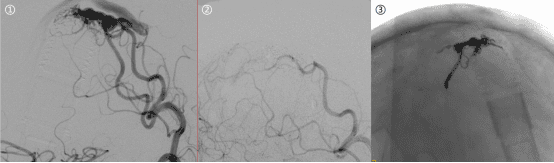

功能区动静脉畸形手术切除致残风险高,介入栓塞可在保留神经功能前提下将畸形血管完全栓塞,不需开颅即可达到治愈的目的。图

1 功能区动静脉畸形,图2 畸形血管不显影,图3 栓塞剂弥散良好